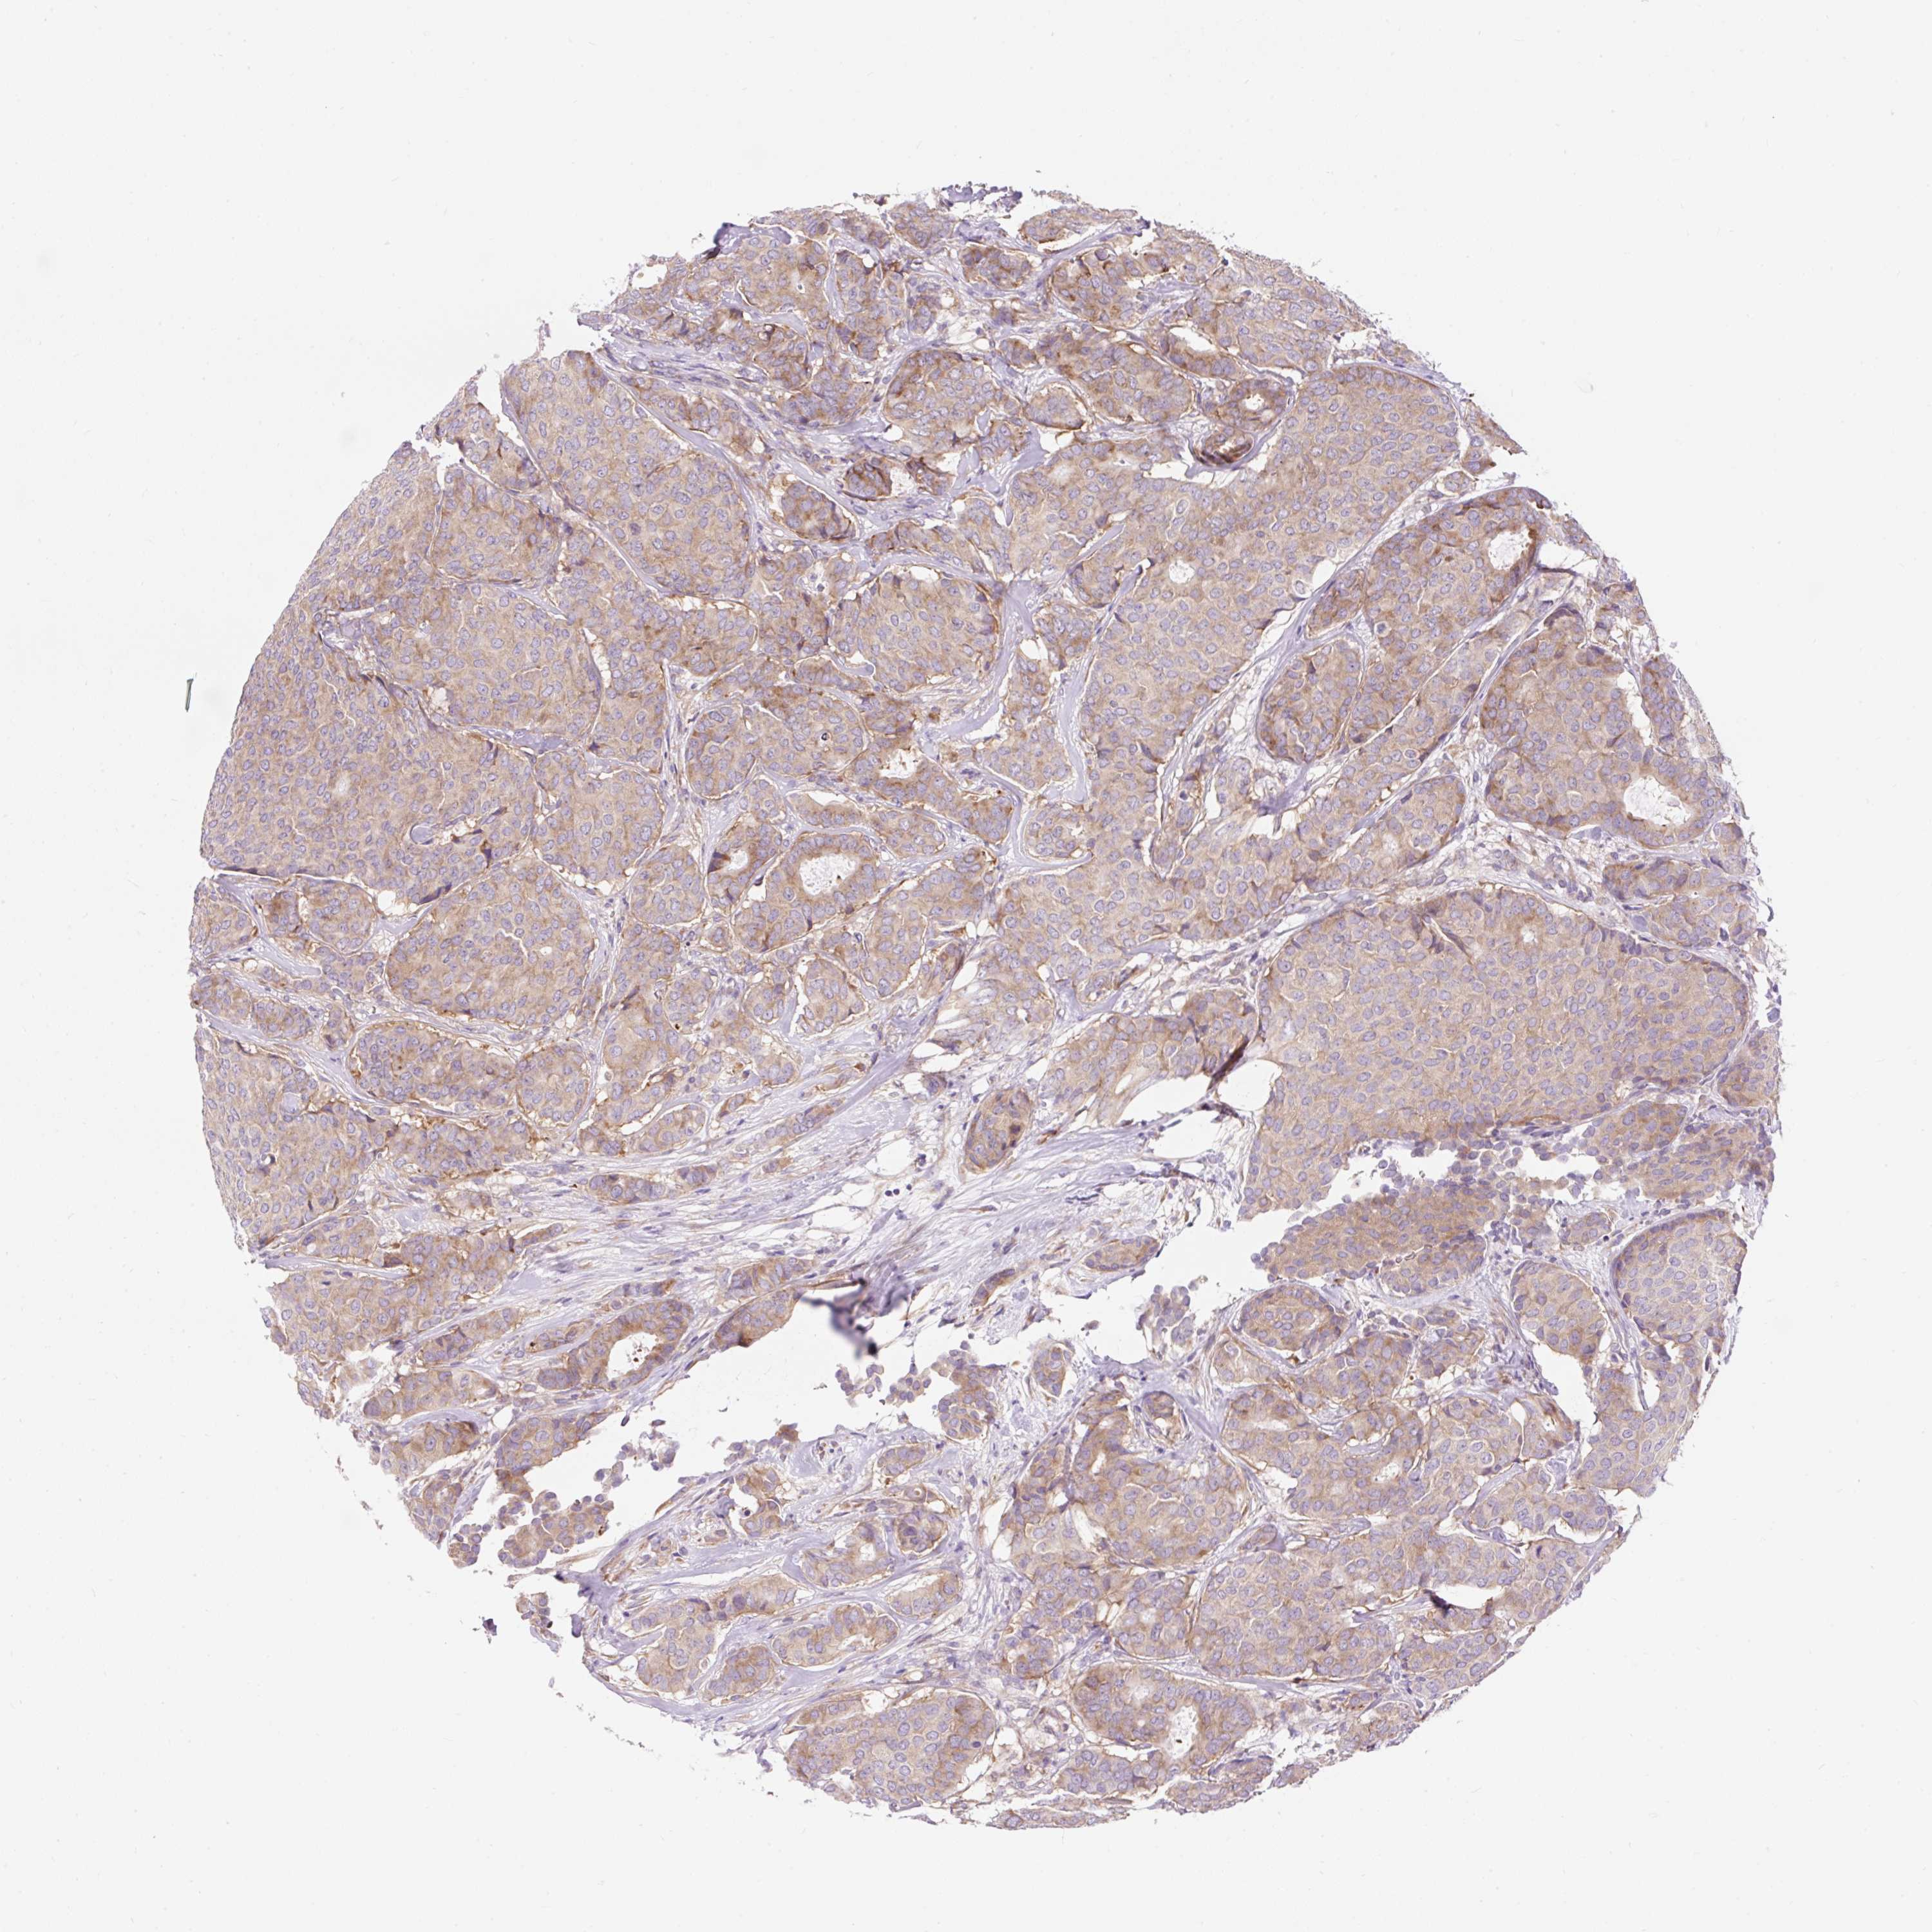

CANCER BREAST CANCER Show tissue menu

BRCA TCGA BRCA VALIDATION PROTEIN EXPRESSION

ANTIBODIES

AND

VALIDATION